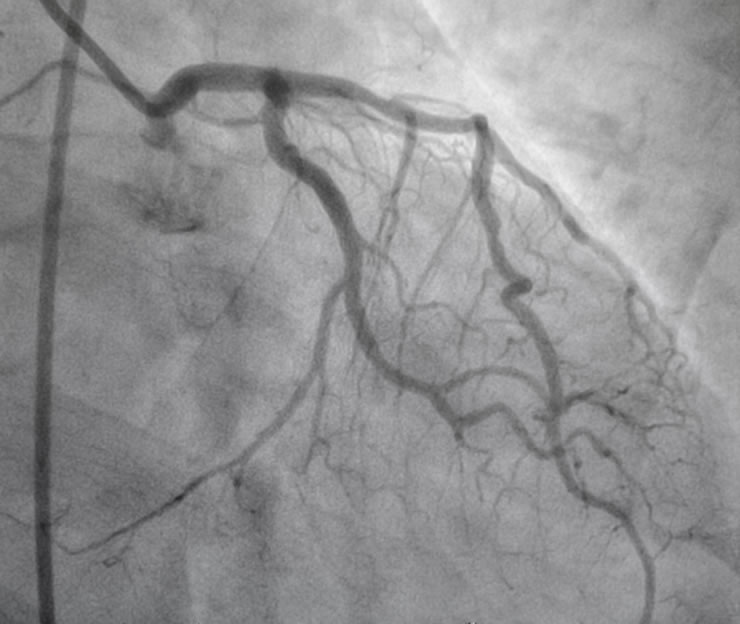

Στεφανιογραφία

Είναι μία ελάχιστα επεμβατική διαγνωστική μέθοδος με την οποία γίνεται ο έλεγχος των στεφανιαίων αγγείων και θεωρείται η χρυσή τομή στην διάγνωση της στεφανιαίας νόσου. Πραγματοποιείται μέσω της κερκιδικής ή της μηριαίας αρτηρίας όπου και τοποθετείται ένα θηκάρι (sheath), διαμέτρου 1.9 χιλιοστών. Μέσω αυτού προωθούνται μέχρι το ύψος της αορτικής βαλβίδας ειδικοί διαγνωστικοί καθετήρες. Εν συνεχεία γίνεται έγχυση σκιαγραφικής ουσίας μέσω ειδικών διαγνωστικών καθετήρων με αποτέλεσμα την απεικόνιση των στεφανιαίων αγγείων.